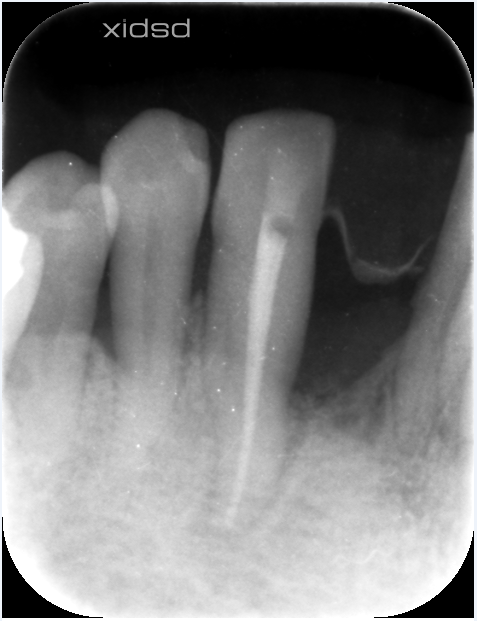

レントゲン

根尖まで骨がなく。。。。グラグラでした。